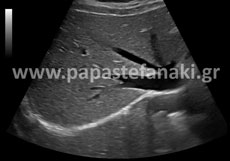

Υπερηχογράφημα ΝΟΚ (Νεφρών - Ουρητήρων - Ουροδόχου κύστης)

Με το υπερηχογράφημα αυτό ελέγχουμε τους νεφρούς, τους ουρητήρες και την ουροδόχο κύστη.